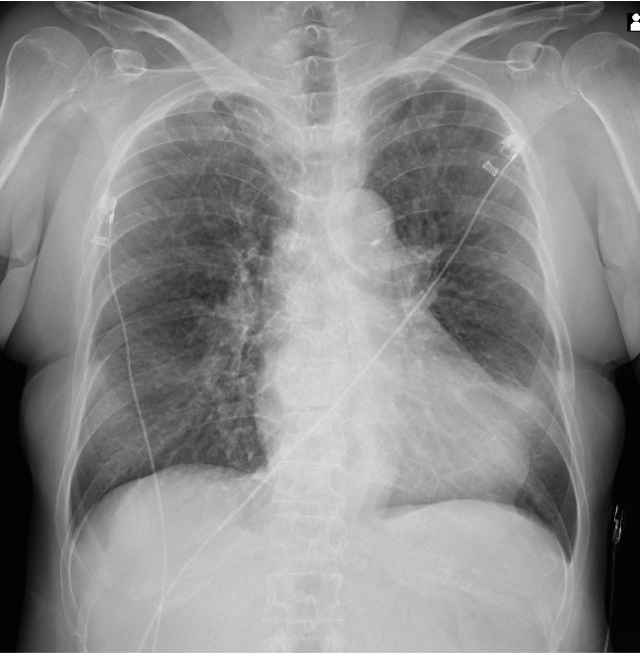

A 66-year-old woman with a history of hypertension and smoking presented with a two-day history of exertional dizziness and general fatigue. On admission, her blood pressure was 93/58 mmHg, and heart rate was 52 bpm. SpO2 was maintained on room air.

Relevant Test Results Prior to Catheterization

A 12-lead ECG showed ST-segment elevation with abnormal Q waves in leads II, III, and aVF, and Mobitz type II AV block was observed. Laboratory tests revealed significantly elevated cardiac biomarkers, with troponin T at 4.289 ng/mL, CK at 1480 U/L, and CK-MB at 46 U/L. Transthoracic echocardiography demonstrated hypokinesis of the inferior wall of the left ventricle and moderate mitral regurgitation. Right ventricular systolic function remained preserved.